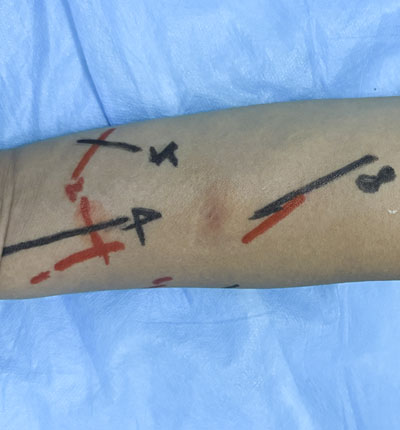

术前定位